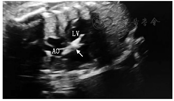

超声心动图评估胎儿的体位,胎儿心尖部朝向孕妇腹壁为最佳位置。孕妇取平卧位,腹部常规消毒铺巾。确定胎位后,超声监视下穿刺脐血管,回抽见血后注入提前根据胎儿体重准备好的芬太尼、阿托品和肌松药,并根据胎儿体重准备抢救药物如肾上腺素、阿托品等。器械主要包括:18 G×15 cm穿刺长套管针(Cook,美国)、22 G硬膜外穿刺长针、0.36 mm×300 cm冠状动脉导丝、4.0 mm× 9.0 mm冠状动脉球囊(Boston Scientific,美国)、压力泵等。术中超声使用Voluson E8 Expert(GE,美国)超声诊断仪,键盘和探头覆盖无菌套。胎儿麻醉后,超声下再次确定胎动明显减少,获得清晰的左心室流出道切面后,确定经皮穿刺点,利用18 G穿刺长针经孕妇腹壁、子宫壁、胎儿胸壁、左心室游离壁后进入左心室,微调穿刺针角度,使其对准主动脉瓣口,拔出针芯后见搏动性鲜红色血流,送入预置的冠状动脉导丝及球囊导管,超声引导下将导丝送至升主动脉,使球囊中部位于狭窄的主动脉瓣处(图1),以生理盐水扩张球囊2~4次,扩张完成后一起撤出穿刺针、球囊及冠状动脉导丝,并检查球囊完整性。术中全程监测胎心及孕妇生命体征。手术取得技术上的成功,术后即刻复查胎儿超声心动图显示主动脉瓣开放改善,前向血流较前增加,压差和流速均有所下降。手术时间约30 min,术后出现少量心包积液(<3 mm),未处理,未出现胎儿心跳过缓和母亲相关并发症。术后4周胎儿的主动脉瓣跨瓣流速和压差明显降低,左心发育情况及血流动力学指标较前有所改善(表1)。

注:LV为左心室;AO为主动脉